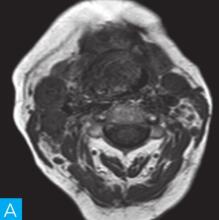

喉咽部MRI检查:病人采取仰卧位,横断位扫描为主,包括T1WI、T2WI及T2WI脂肪抑制序列,扫描范围自鼻咽部至喉咽以下,扫描层厚为3.5mm、层间隔0.35mm,矩阵512×512;辅以冠状位T2WI,矢状位T2WI序列及脂肪抑制序列,平扫后行横断位、冠状位及矢状位的增强扫描,造影剂量0.2ml/kg。见图1。

图1 咽喉部MRI:A.喉咽部MR横断面平扫T1WI;B.喉咽部MR横断面T2WI;C.喉咽部MR横断面T2压脂;D.喉咽部MR横断面增强T1WI;E.喉咽部MR冠状面T2WI;F.咽喉部MR冠状面增强T1WI

MRI平扫可见右侧扁桃体较大的软组织肿块,T1WI呈稍低信号,T2WI呈稍高信号,信号较均匀,T2WI压脂序列上呈高信号,病变与右侧咽扁桃体及舌根部分界不清,左侧咽扁桃体肿大,口咽腔明显变形狭窄,病灶延伸至喉前庭;双侧锁骨上窝及颈血管鞘周围间隙内可见多发大小不等的肿大淋巴结,大部分肿大淋巴结信号较均匀,呈稍高信号,边界清楚,右侧颈部间隙内个别肿大淋巴结内见少量斑片状液化坏死区;增强扫描后下咽部病变及双侧颈部间隙内的肿大淋巴结均呈明显的较均匀强化,提示该两处占位病变的血供较为丰富,且可能为同源性病变,因此采取“一元论”诊断思维进行分析更为合理。

(1)发现病变与认证:扁桃体及颈部病变较为容易发现,主要是分析两方面:一是仔细观察咽部有无原发病变,原发病变的形态及信号;二是评价淋巴结的分布,淋巴结的信号及生长特点。本病例基本征象为扁桃体病变信号均匀,无坏死,颈部淋巴结分布广泛,信号均匀。

(2)定位诊断:对于本病例来说,发现两处病变,包括咽部和颈部。咽部的病变位于扁桃体,延伸至喉咽腔,口咽腔和梨状窝受压变窄。颈部的病变为多发淋巴结增大,淋巴结广泛分布于Ⅱ~Ⅴ区。

本病例的特点为右侧扁桃体肿块,病变边界较清楚,表面光滑,信号均匀。双侧颈部间隙内多发肿大淋巴结,淋巴结围绕颈动脉鞘,部分病变融合倾向,广泛分布于Ⅱ~Ⅴ区,增强后病变较明显强化。

该病例首先对病变进行定位,包括咽部的和颈部的。咽部的病变:病变位于扁桃体,延伸至喉咽腔,口咽腔和梨状窝受压变窄(引起异物感和吞咽困难的原因)。颈部的病变:多发淋巴结增大,淋巴结广泛分布于Ⅱ~Ⅴ区。扁桃体病变的信号特征:扁桃体病变表面光滑,提示黏膜完整,病变来源于黏膜下,病变信号均匀,无坏死,进一步支持病变来源于黏膜下。颈部淋巴结病变的特征:淋巴结分布广泛,信号均匀(可以初步排除结核和转移,后两者容易坏死),围绕颈动脉鞘,但是不侵犯颈动脉鞘(转移容易侵犯颈动脉鞘),部分淋巴结融合倾向(结核淋巴结增大,无融合倾向,而且容易坏死),病变中度强化,进一步支持颈部淋巴瘤的诊断。诊断原则:首先仔细观察咽部有无原发病变,原发病变的形态及信号,尤其黏膜是否完整。其次评价淋巴结的分布,淋巴结的信号及生长特点。